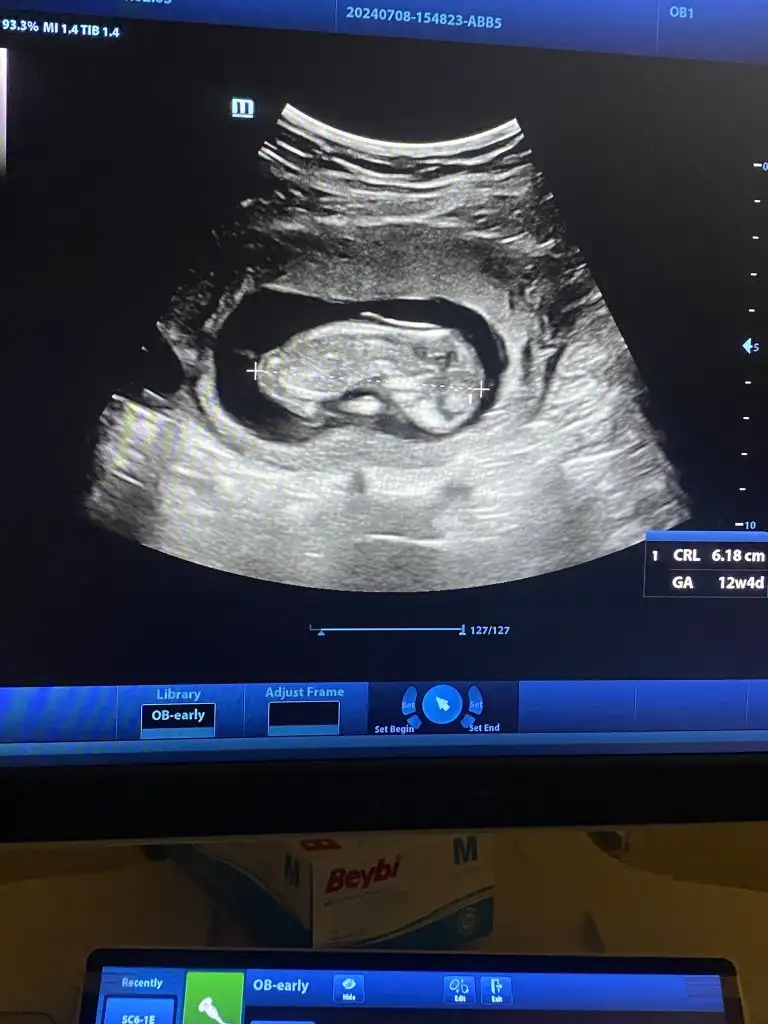

Böyle fotoları görünce Cinsiyet için 13 haftayı beklemek istemiyorum yaa Dr 12. Haftada gel dedi ben 13 te giderim diye kendimi ofakladım ama şimdi böyle paylaşımları görünce kendime engel olamıyorumBugün kontrol vardı bizim kız totosunu gösterdi bize amuda kalkmıştı rahmimde![]()

Biz fetal dna yaptırdık bi hafta önce öğrendik valla dayanması çok zor gerçektenBöyle fotoları görünce Cinsiyet için 13 haftayı beklemek istemiyorum yaa Dr 12. Haftada gel dedi ben 13 te giderim diye kendimi ofakladım ama şimdi böyle paylaşımları görünce kendime engel olamıyorumçok çok tatlı yaa